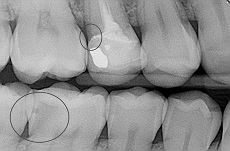

b) snímek k detekci – zjištění mezizubních kazů (anglicky: bite wing) - zobrazuje nově vzniklé kazy v mezizubním prostoru, kvalitu již zhotovených výplní, druhotné kazy vznikající v okolí výplní. Provádějí se od trojek dozadu (čili 4-8 na každé straně v horní i v dolní čelisti), kde je v sousedství zubů široký sklovinný val, přes který mnohdy kaz není v počátečních stádiích vidět nebo je lehce přehlédnutelný.

Foto 3-5: Pořízení snímků ke zjištění mezizubních kazů, které jsou označeny kroužkem.